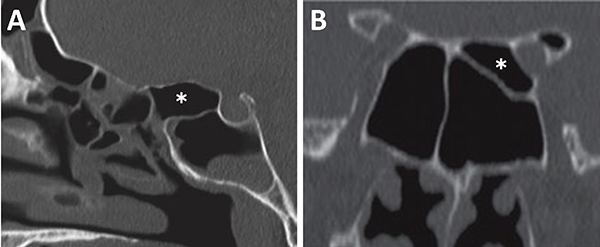

La identificación de ambos nervios ópticos en la tomografía toma relevancia por una potencial lesión iatrogénica. Se debe identificar a los mismos y valorar su trayecto principalmente cuando el seno esfenoidal y/o etmoides posterior presentan gran neumatización. Éstos pueden estar completamente cubiertos por hueso o presentarse dehiscentes (fig. 14).

El grado de neumatización de etmoides posterior es variable. Se debe identificar si existe hiperneumatización del mismo, con extensión de celdillas a región superior y lateral se seno esfenoidal, variante que conocemos como celdas de Onodi. Su relevancia radica en mantener durante el intraoperatorio un adecuado corredor hacia la hipófisis, y evitar una “falsa vía”, con potencial lesión intracraneal (fig. 15).

Figura 14: Localización de nervio óptico en TC cortes coronales. A) Nervio óptico dehiscente; B) Nervio óptico en su meso, con variante hiperneumatizada esfenoidal.

Figura 15: Hiperneumatización de etmoides posterior. A) TC corte sagital; B) TC corte coronal, obsérvese la celdilla de Onodi (asterisco blanco).